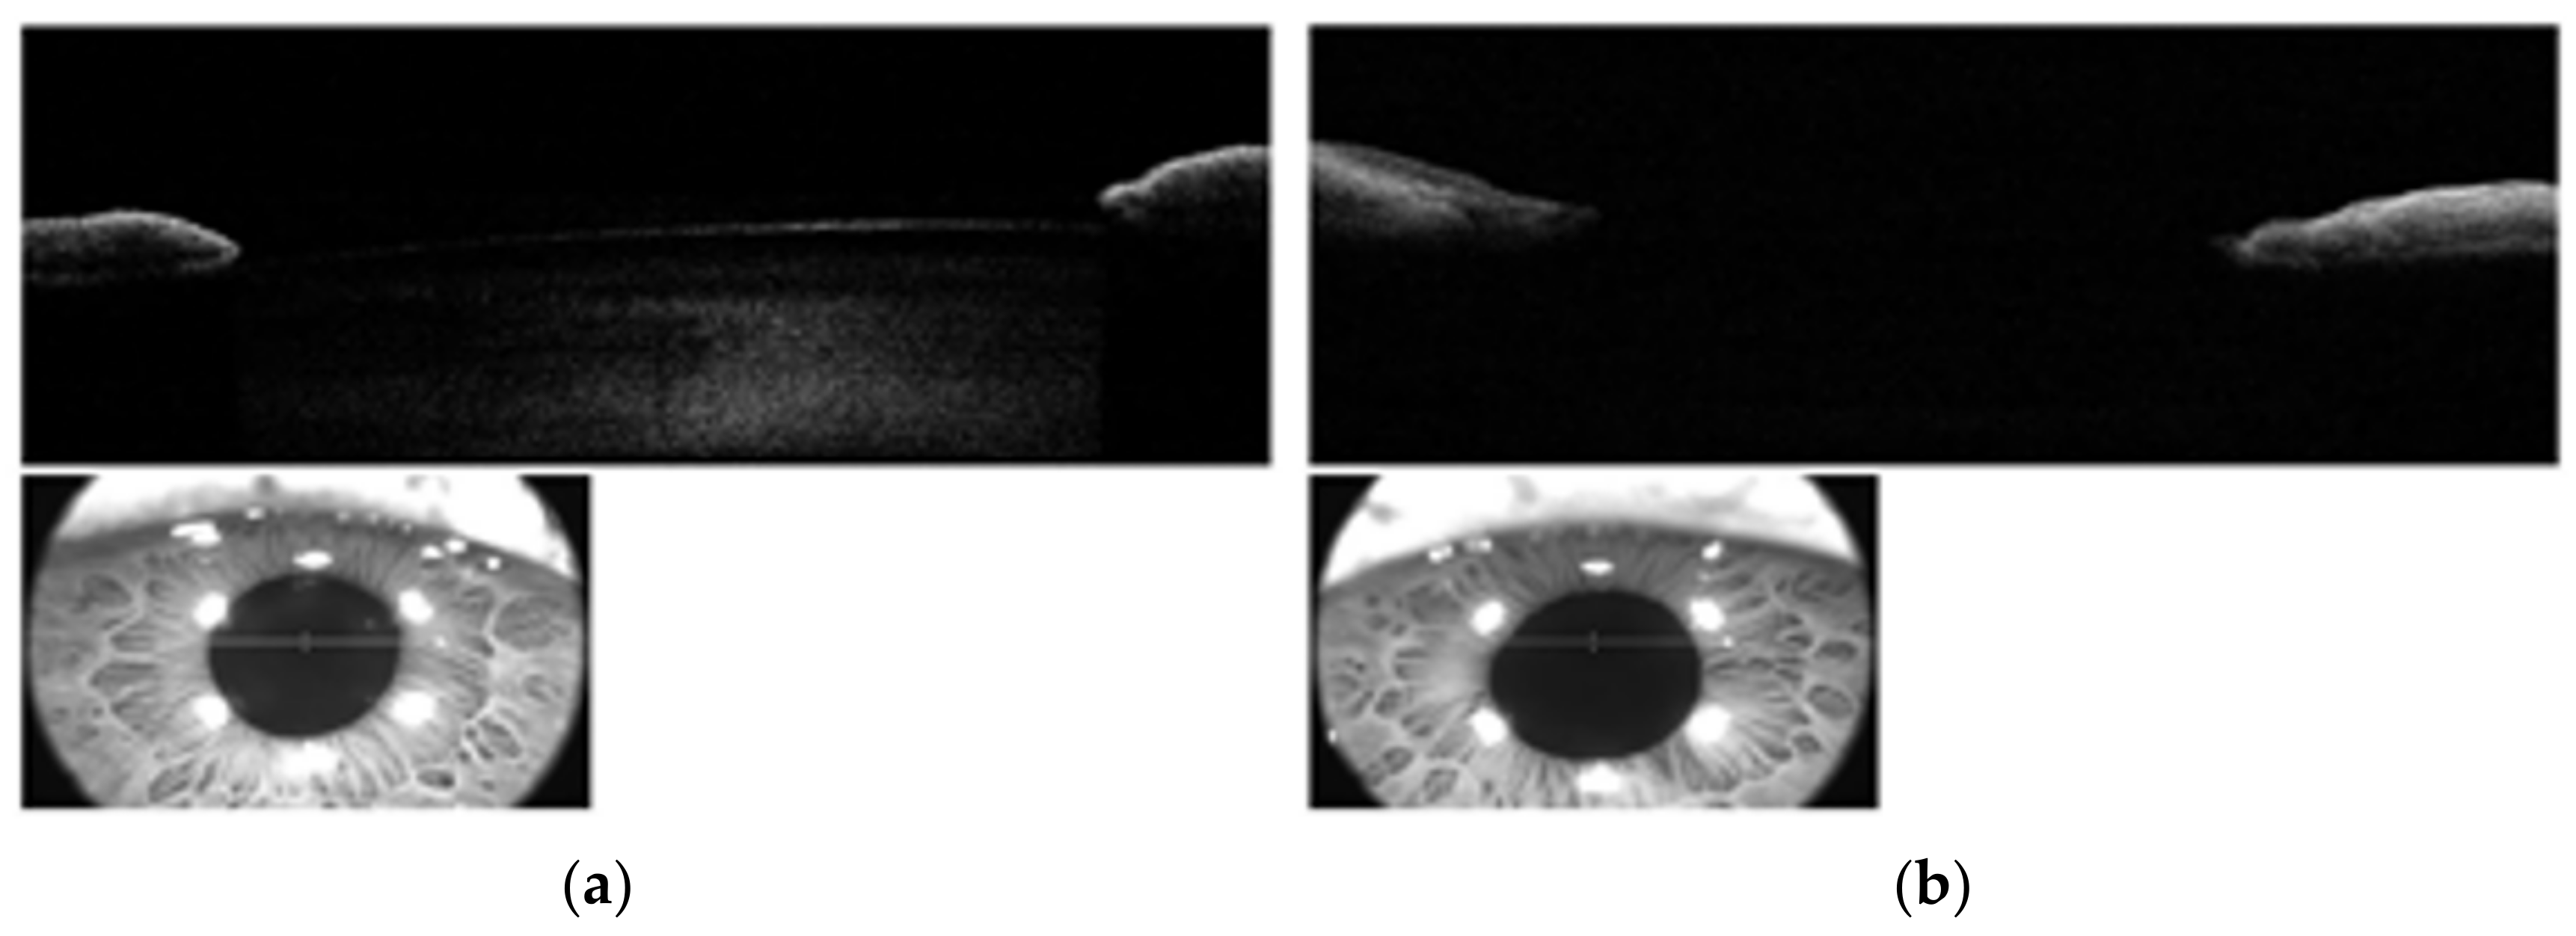

2. Case Presentation